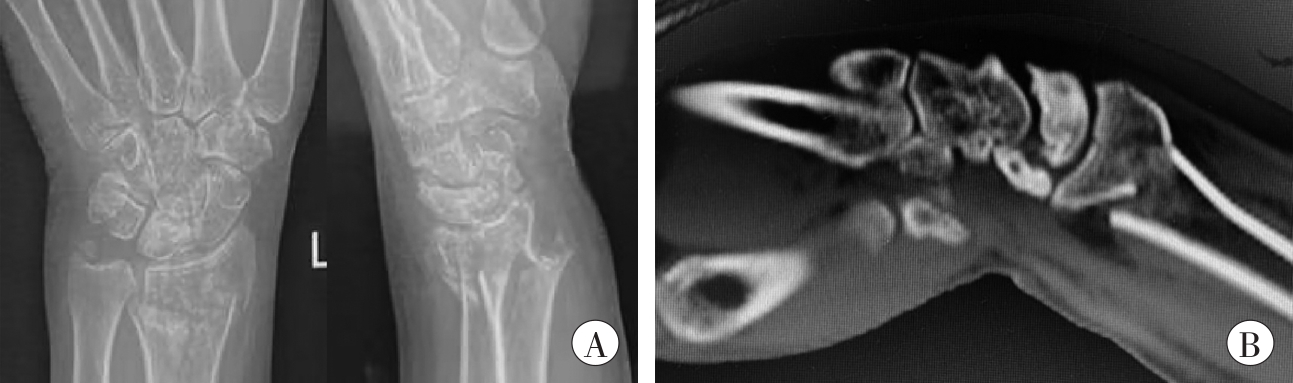

图1 受伤当日影像学检查结果

A:X线片;B:CT片。

Fig. 1 Imaging examination results on the day of injury